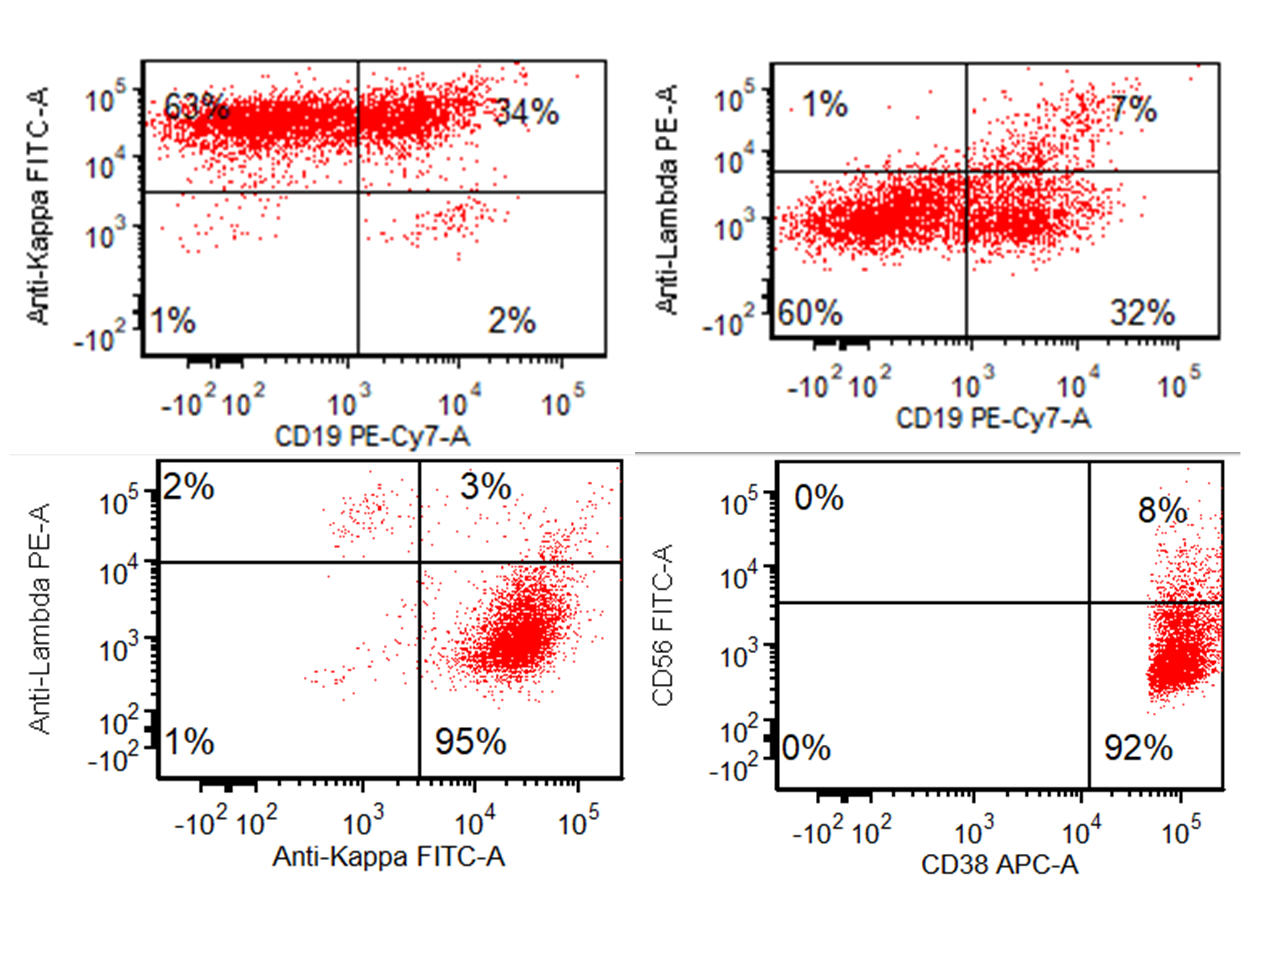

Flow cytometry description

- Monotypic cytoplasmic Ig and usually lack surface light chain

- Express CD38, CD138, often CD56+ or CD117+; may have partial CD45, usually negative for CD20, CD19 and CD10 (Cytometry B Clin Cytom 2016;90:61)

- Exception in myeloma with t(11:14) where plasma cells more often express B cell markers including CD19 and CD20

Flow cytometry images